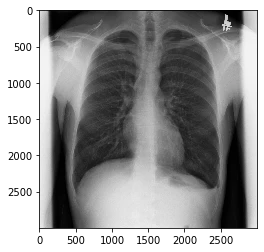

ImageJのアルゴリズムを用いたダウンスケール

ImageJのダウンスケールを実装してみました。

最大値、最小値と、スケーリングファクタで正規化します。

# ImageJから拝借したノーマリゼーション

amin=np.amin(pixels_)

amax=np.amax(pixels_)

pixelsByte = ((pixels_-amin)/(amax-amin))*255

# pixelsByte = ((pixels_-amin)/(amax-amin+1))*256

pixelsByte = np.clip(pixelsByte,0,255)

pixelsByte = np.uint8(pixelsByte) # 符号なしバイトに変換

print(np.asarray(pixelsByte)[512,512])

plt.imshow(pixelsByte,cmap="gray")

plt.show()

これこれ。求めてた画像です。